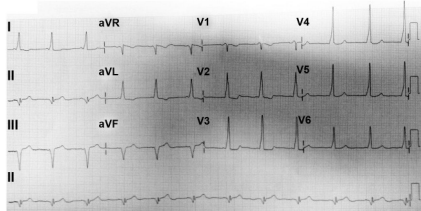

O eletrocardiograma abaixo, obtido durante a crise de taquicardia, sugere qual diagnóstico

Na doença demonstrada no eletrocardiograma abaixo, observamos que: